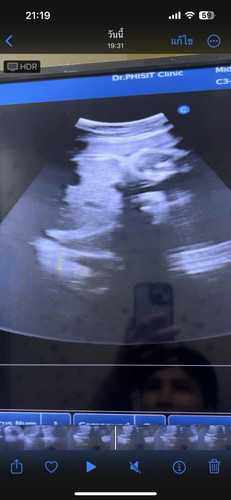

แบบนี้ผู้หญิงรึป่าวค่ะซาวรอบแรก21วีคหมอบอกผู้ชายแต่วันนี้32วีคหมอซาวแม่ถ่ายคลิปมาทำไมไม่เห็นอะไรโผล่เลย

เราเห็นเป็นกลีบค่ะ ถ้าเป็นผู้ชายอวัยวะเพศจะขึ้นโด่เลย (บางคนหนีบก็อาจจะทำให้คิดว่าเป็นผู้หญิงได้ค่ะ) ตอนนี้คุณแม่ซื้อเสื้อผ้าน้องมาแล้วใช่ไหมคะ